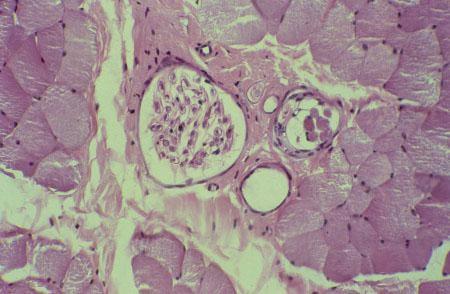

V-75 (4) K Slide 25, Muscle Spindle (H&E). A muscle spindle (right) and a large nerve bundle (left). Intrafusal fibers are inside the spindle and are smaller than extrafusal fibers which are outside the spindle.